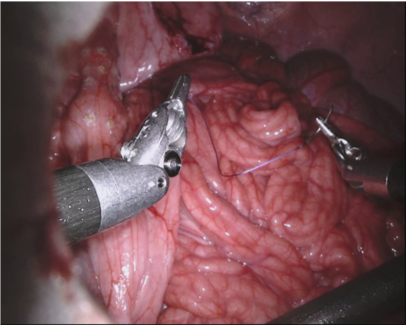

Our challenge was made up of 3 sub-problems. The first was binary instrument segmentation, where each frame was separated into da Vinci Xi instruments and a background class, which contained an ultrasound probe, surgical clips and porcine tissues. The second task was instrument part segmentation, where we scored the participants on whether they could correctly segment each articulating part of the instrument (see Fig. 3). Our final task was to segment and classify the instruments (see Fig. 4).

We provided the first 225 frames of 8 sequences as training data and kept the last 75 frames of those 8 sequences as test data. 2 of the full 300 frame sequences were kept as test sequences. Test labels were kept hidden from the participants. Our datasets contain 7 different robotic surgical instruments. The Large Needle Driver, Prograsp Forceps, Monopolar Curved Scissors, Cadiere Forceps, Bipolar Forceps, Vessel Sealer and additionally a drop-in ultrasound probe, which is typically held in the jaws of the Prograsp Forceps instrument. Samples from the training datasets are depicted in Fig. 2 and examples of the different instrument types are shown in Figure 3 and 4.